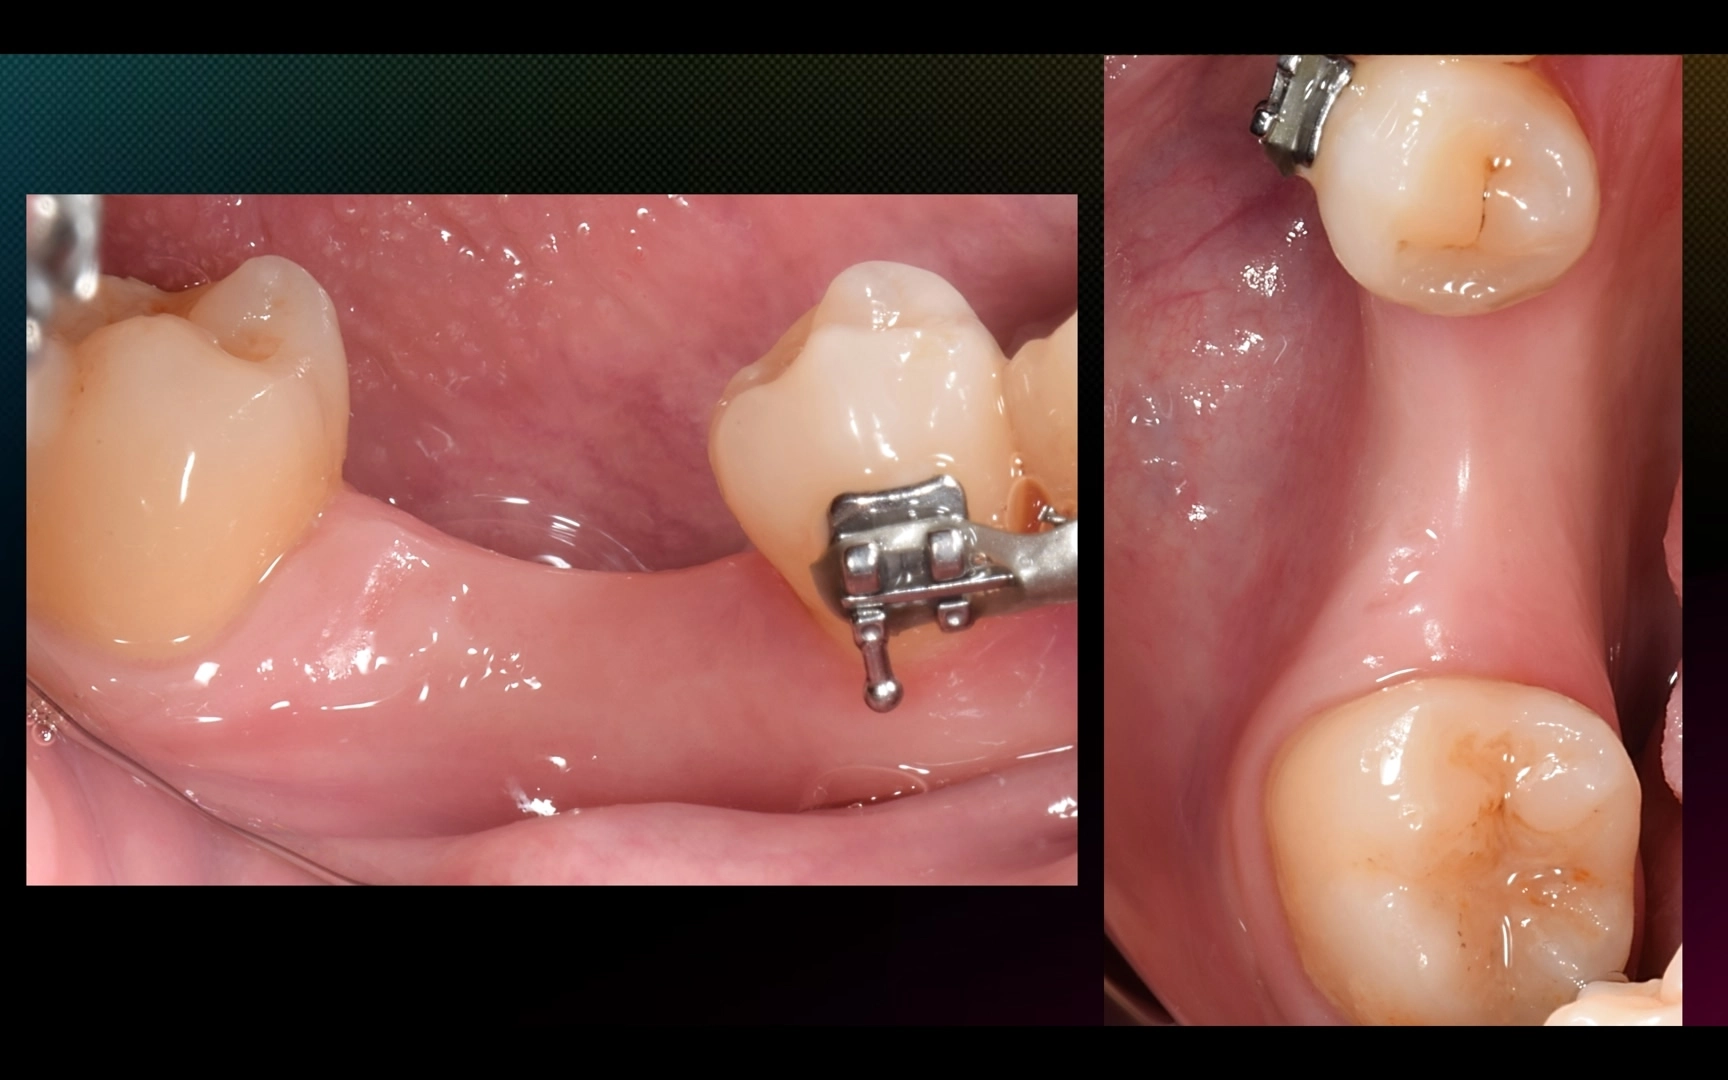

2. Через 5 месяцев после имплантации (пациентка раньше не смогла, обычно на н/ч выжидаем 3 месяца) — установка коронки с помощью ортопедического расщепления мягких тканей.